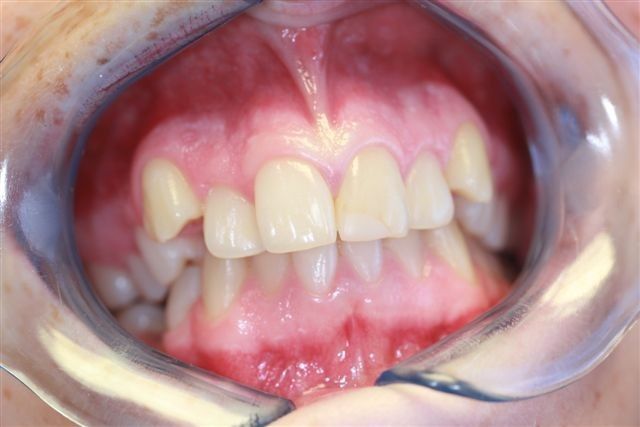

Junge Frau mit Zahnspange beim Zahnarzt